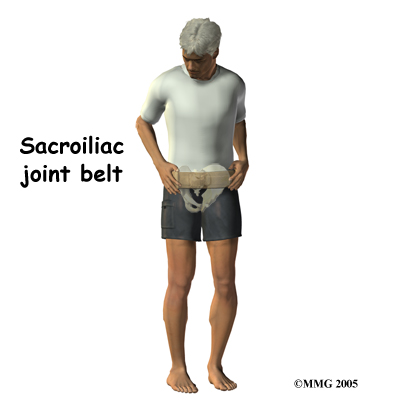

If the SI joint has too much mobility and problems keep coming back, you may need extra help to stabilize the SI joint. Some patients benefit from wearing a special brace called a sacroiliac belt. This belt wraps around the hips to hold the sacroiliac joint tightly together, which may ease your pain. A belt like this can often ease pain enough to let you exercise comfortably.